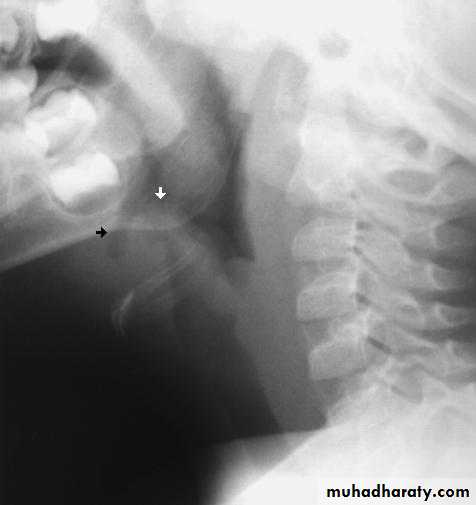

Lateral X-ray of the neck may show swollen epiglottis (thumb sign).Treatment